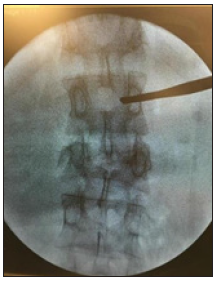

Pedicle taping was done from lateral margin up to the medial margin as in AP view Figure 3. At this point, we must take a lateral view (Figure 4 & 5); it is very important step to make sure about the position of the tab cannula as it might be

Figure 3:

Figure 4:

Figure 5: